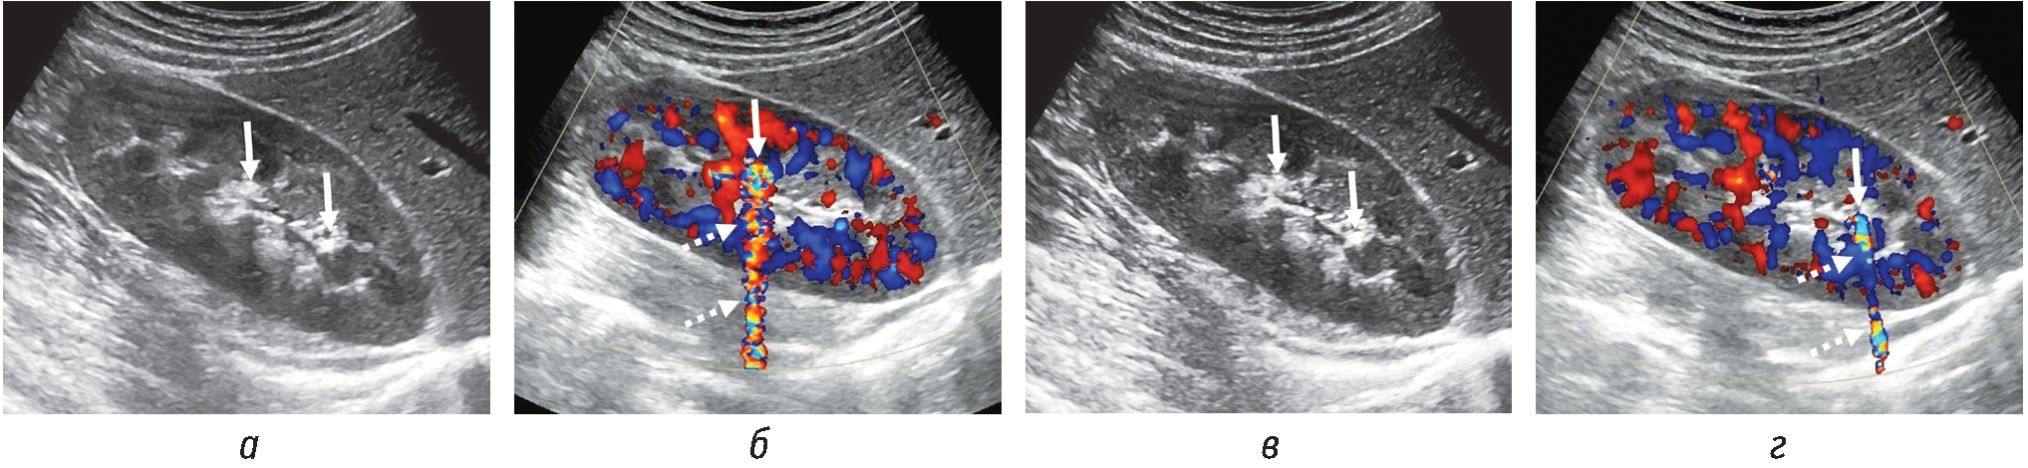

Более того, особенно интересно следующее наблюдение: у 90 % пациентов с ложноположительным АМ нефролитиаз в том или ином виде может визуализироваться на КТ-снимках по меньшей мере в одной из почек, даже если область визуализации не совпадает с локализацией АМ при ЦДК. С другой стороны, интересен и тот факт, что, даже несмотря на визуализируемый конкремент в B-режиме УЗИ, а также на подтверждение его наличия при помощи бесконтрастной КТ, АМ в режиме ЦДК у части пациентов отсутствовал [8]. Это еще раз подчеркивает сложность природы АМ и необходимость рассматривать не только сам факт его наличия или отсутствия, но и особенности как структуры конкремента, так и уродинамики в целом (рис. 3).

Рис. 3. Трансабдоминальные сонограммы (а, б) и бесконтрастные КТ-снимки (в, г) пациентки 49 лет: а — конкремент (сплошная стрелка) 6 мм в расширенной чашечке без четкой АТ; б — соответствующая сонограмма в режиме ЦДК, АМ указан пунктирной стрелкой; в и г — тот же конкремент, визуализируемый на снимках по длинной (в) и короткой (г) осям почки соответственно. Трансабдоминальные сонограммы (д, е) и бесконтрастные КТ-снимки (ж, з) пациента 60 лет: д — два конкремента (сплошные стрелки) 3 и 4 мм, без акустической тени, в юкставезикальном отделе правого мочеточника; е — соответствующая сонограмма в режиме ЦДК; АМ указаны пунктирными стрелками; ж и з — снимки бесконтрастной КТ в аксиальной плоскости, проведенной через 15 мин после УЗИ, — один конкремент по-прежнему в юкставезикальном отделе правого мочеточника (ж), а второй сместился в интрамуральный отдел правого мочеточника (з). Белым кругом обведен флеболит